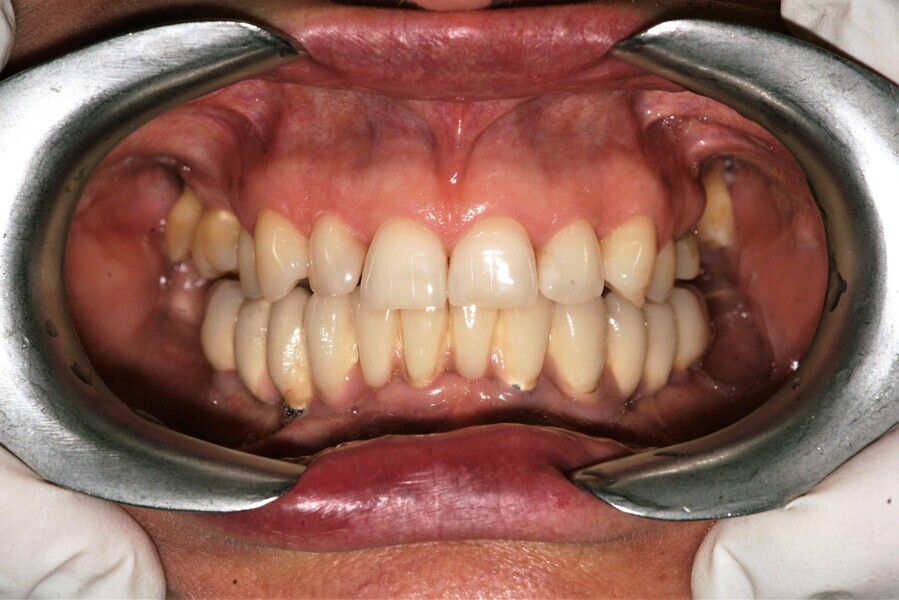

Natychmiastowa implantacja i zaopatrzenie protetyczne pacjentów z zaawansowaną chorobą przyzębia